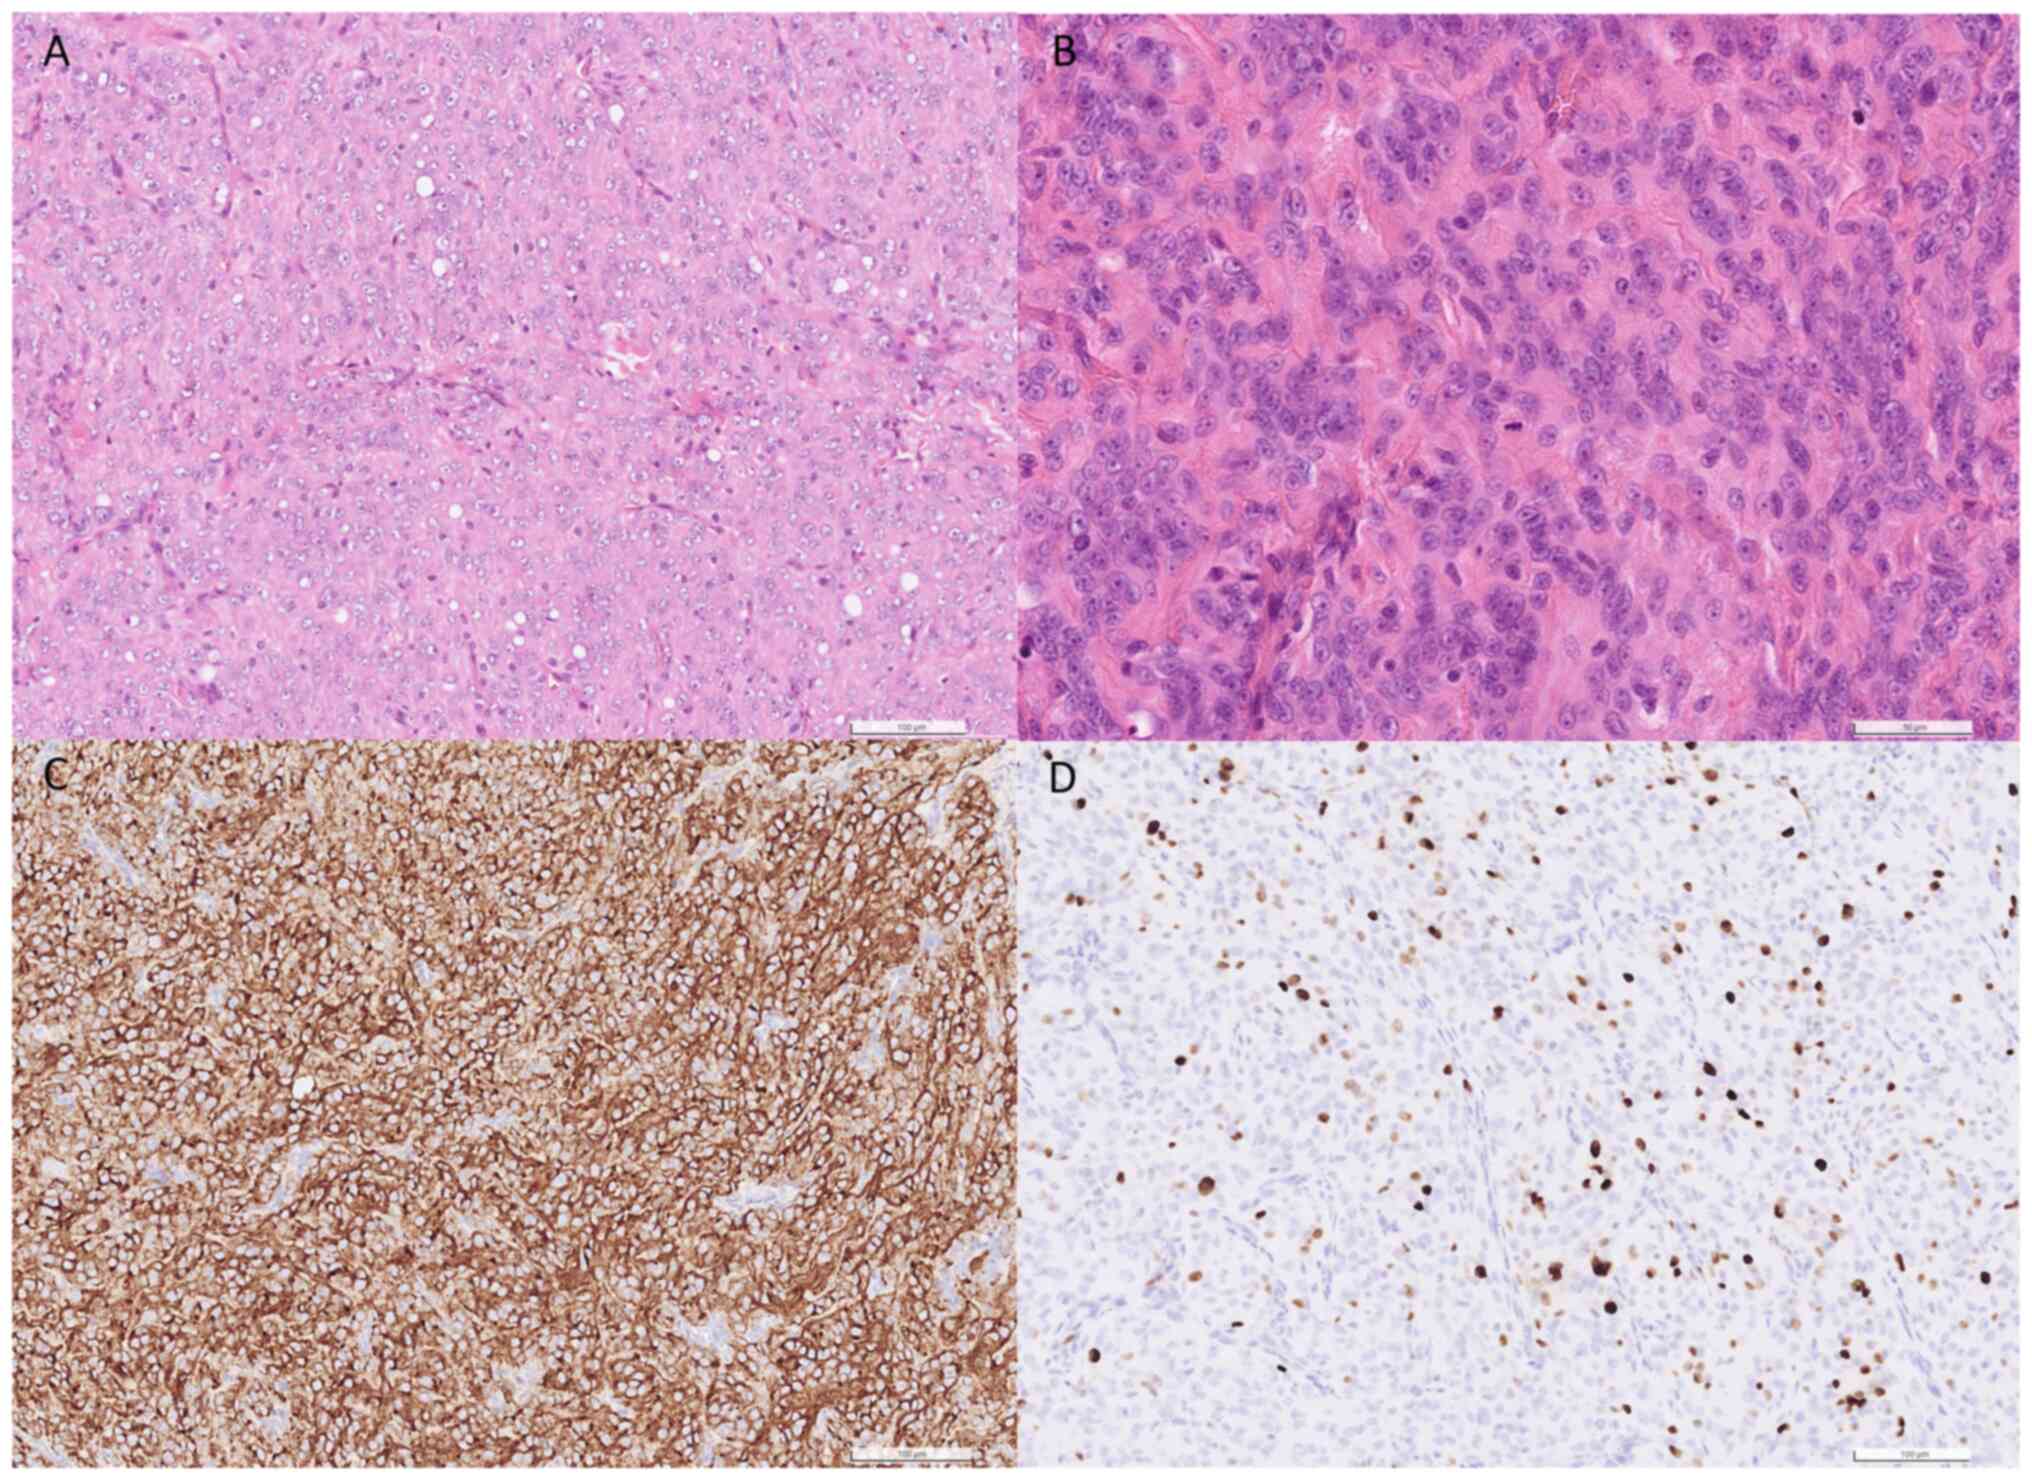

and then cut into 4- to 6-µm thick sections. Hematoxylin and eosin

staining was performed at room temperature using Mayer's

hematoxylin solution for 15 min and eosin solution for 40 sec.

Sections were observed using a light microscope (Olympus BX51) with

a digital slide scanner (Hamamatsu NanoZoomer S360). The

proliferation of epithelioid to spindle tumor cells was observed.

Furthermore, a sheet-like growth pattern, focal necrosis and

increased mitotic activity were also observed (Fig. 3A and B).

using a light microscope. IHC analysis indicated positive reactions

to EMA and SSTR2 and negative reactions to S100 and SOX10 (Fig. S1A-C). This distinct immunoprofile

serves a role in differentiating this tumor from neurogenic mimics,

such as cellular schwannoma or malignant peripheral nerve sheath

tumor.

The Ki-67 labeling index was determined to be 15%.

Based on these pathological characteristics, the tumor was

classified as a World Health Organization Grade II atypical

meningioma (12) (Fig. 3C and D).